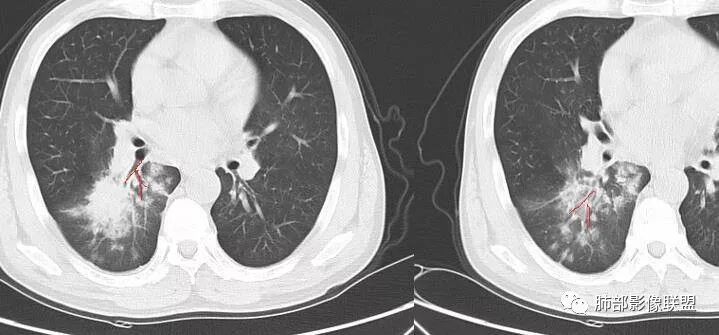

病灶近端支气管通畅,局部体积缩小不明显,外围大内带小,沿支气管树蔓延过来

高海峰:中老年男性,急性起病,右肺下叶背段片状影,支气管略窄,边缘收缩平直,周围见班片状影,肿瘤,淋巴瘤。南边:个人倾向于炎性,结核可能没意见:图不够多,背段、上支是不是截断了?外支好像截断了

远端确实有膨隆,边缘凹凸不平,换个角度,这个病灶紧贴着斜裂外带。

南边:紧贴着斜裂过来的一个病灶,它的特点是:外围大,内带小。它整个下叶背段体积与对侧相比稍微缩小一点,但是缩小地不是很厉害。外支朝前下走了,仔细看血管,肺动脉走行自然,直达远端。远端实变区是肉芽肿成分,稍微有一点低密度,没有明显坏死,稍微有一点点坏死。而且附近有很多卫星灶,附近很多斑片影,有一些明显有气道壁增厚,细支气管炎的特点,还有就是下叶其他段很多斑片状影。换个角度,第一如果是肺癌,刚才看到PET-CT提示肺癌伴阻塞性肺炎,这个是不符合的。第二如果是肺癌阻塞性肺炎,近端血管肺动脉走行不会那么自然集聚的,这个是不符合的。理由是:如果这个病灶是肺癌,那么明显属于中央型肺癌,中央型肺癌的特点是近端大,远端小,近端是一个肿块,远端阻塞,远端阻塞是阻塞性炎症或者不张,它应该体积缩小,斑片状实变,不会这么密实。刚才有老师提到支气管,这个片有缺陷的地方,给的图像好像那层,如果把其他图像拿开再重叠一下。

鉴别诊断:肺炎性肺癌,胸膜下起源,外围大,局部占位效应,有膨隆有收缩,这个不太支持。支气管走行里面没有看到支气管进入很自然堵塞的粘液栓的特点。附近这些磨玻璃影,它的磨玻璃影要么边界清楚,要么由内朝外蔓延的,而不是沿着支气管束蔓延的。而且附近斑片状影,有些似乎有结节感,但是大部分不是,它不是我们常见的磨玻璃样结节,有些有,导致像腺泡样结节那种椭圆的沿着血管束分布的,我会把肺炎型肺癌放在待排。